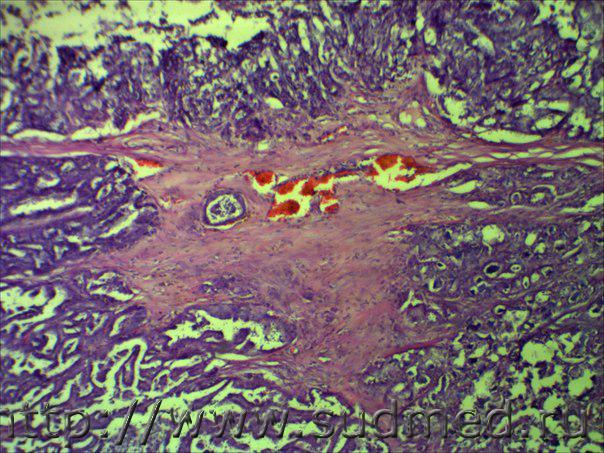

Плотное,множественное, размером с "ноготь".

Медик На фото нет чёткости,но похоже на внутрипротоковый... 31.10.2014 - 14:01

доктор морфолог Плотное,множественное, размером с "ноготь... 3.11.2014 - 07:57